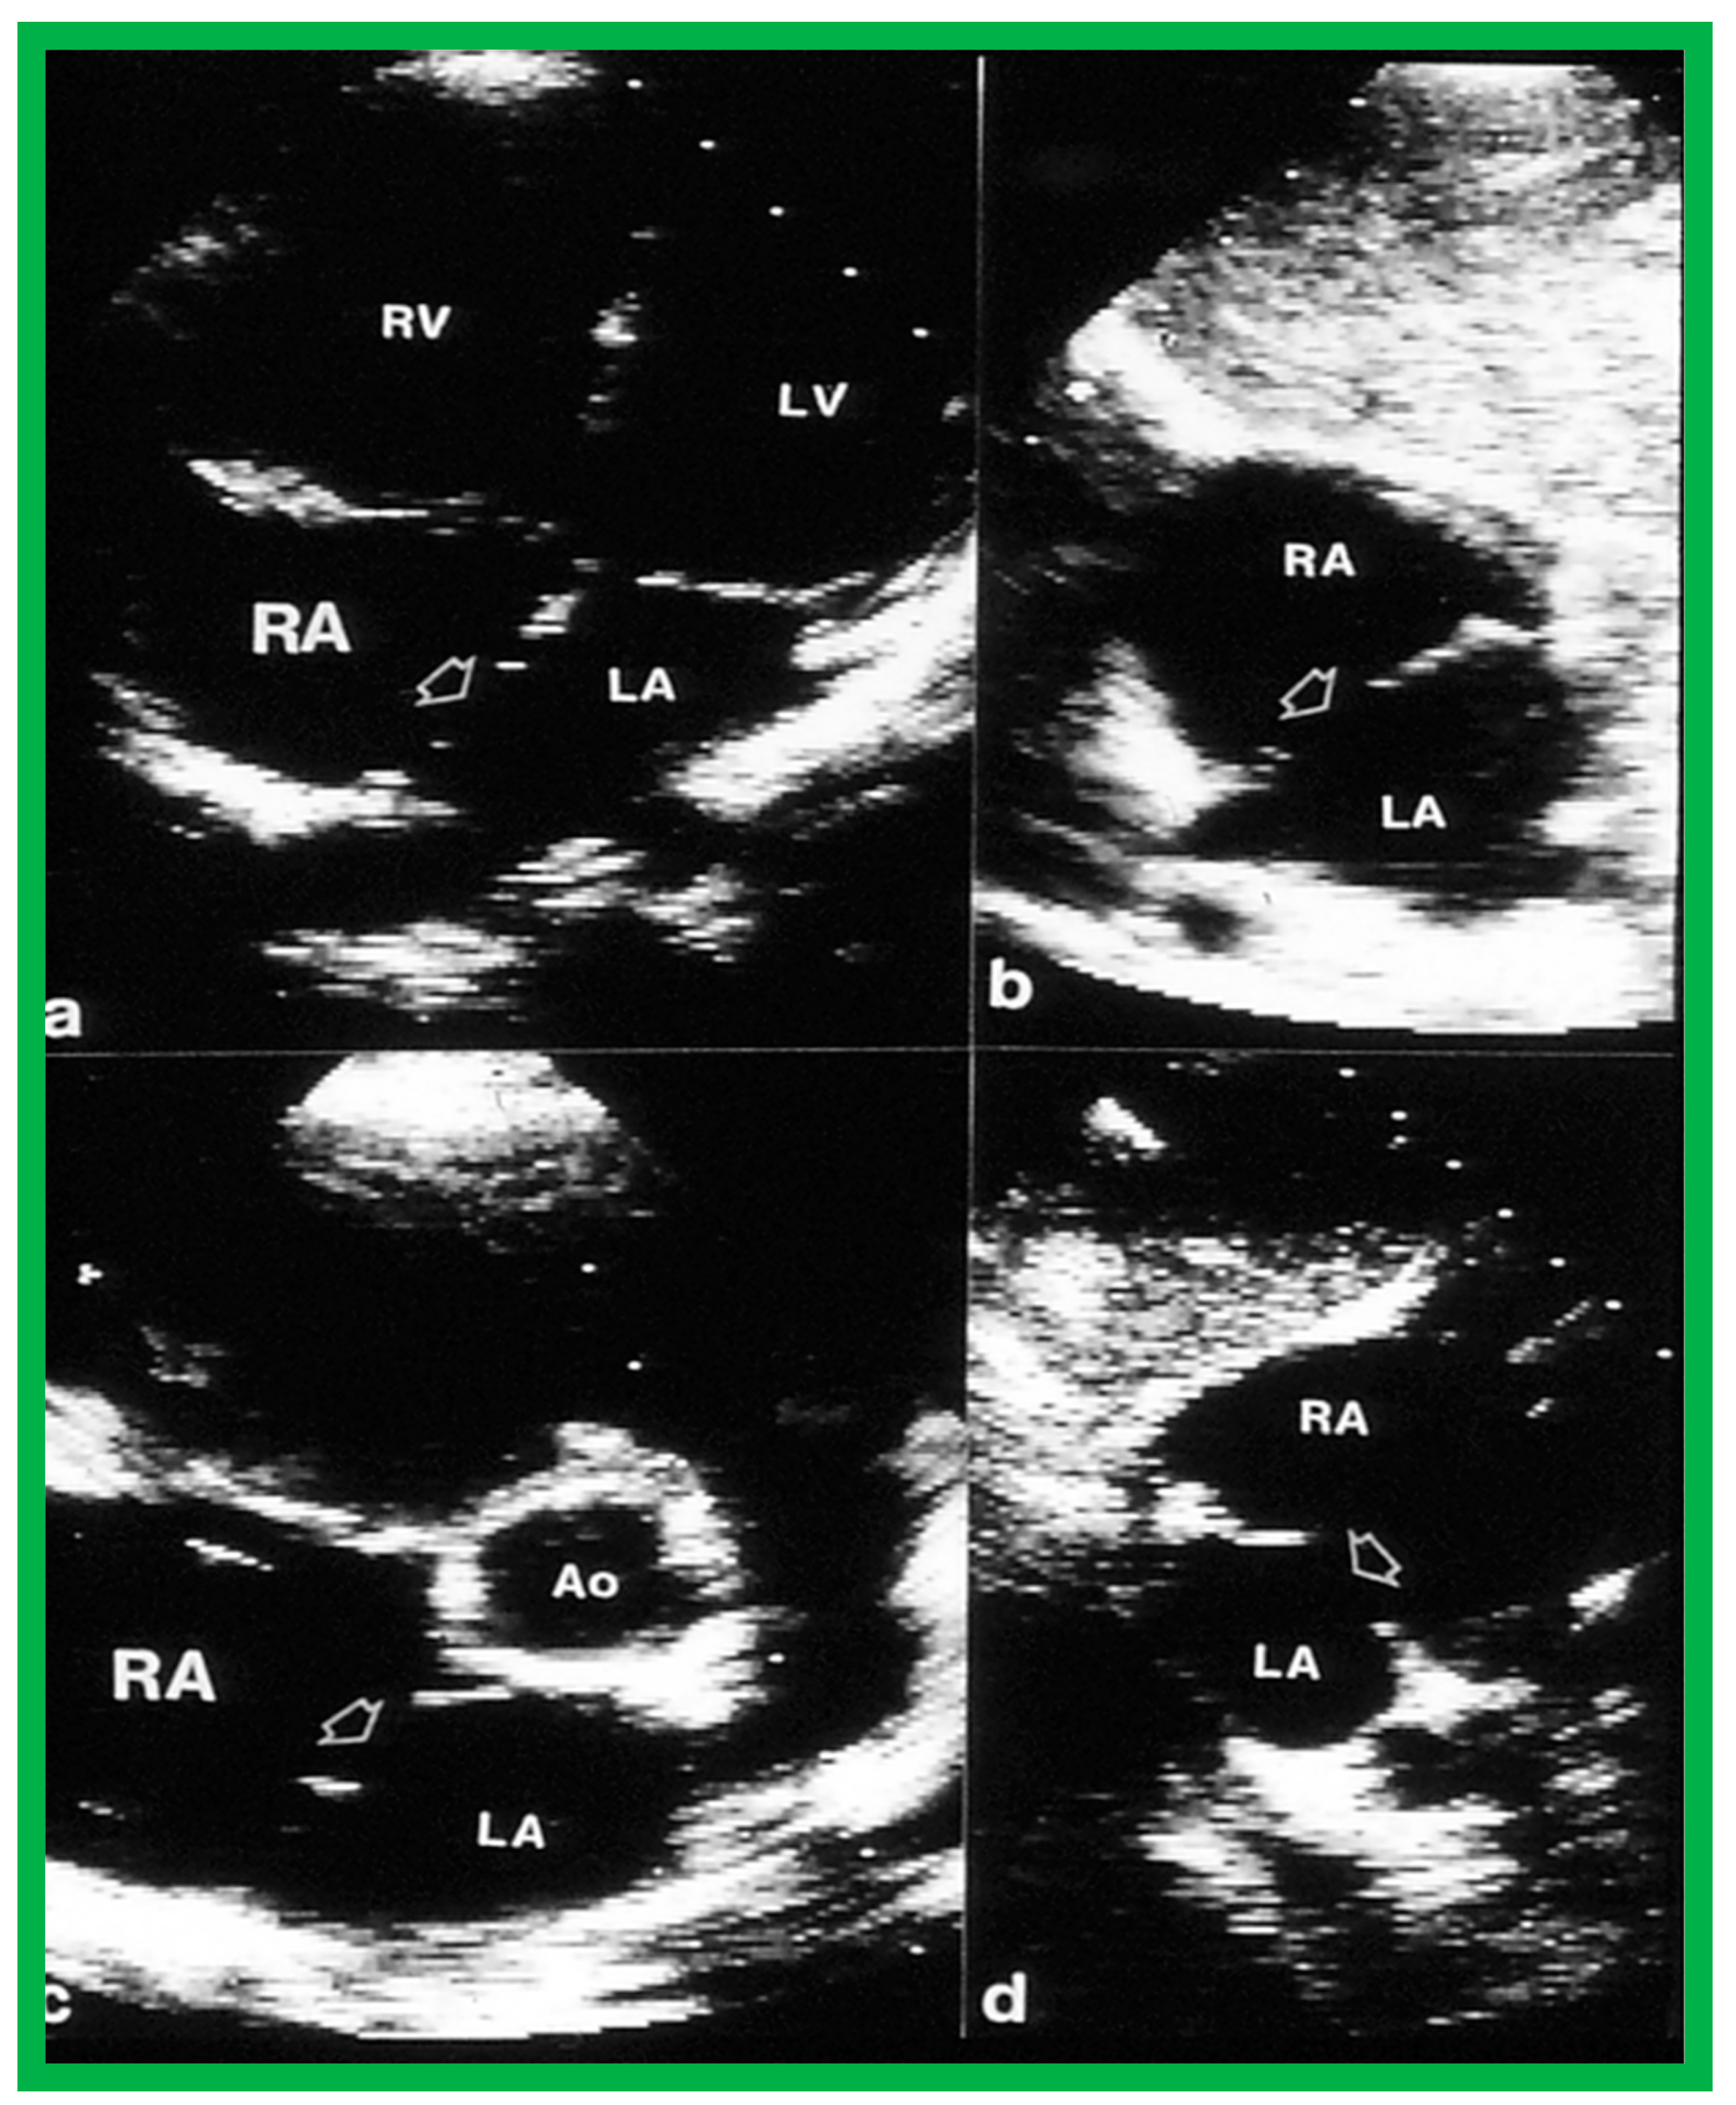

2. Diagnosis